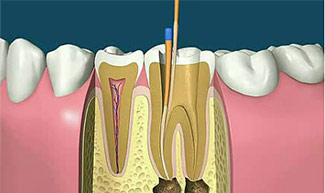

根管治疗

安全微痛,根治多种牙齿病症

- 1/根管预备

- 1/根管冲洗

- 1/根管冲洗

- 1/根管填充

适应症:

急性或慢性牙髓炎、根尖炎症、牙髓暴露感染、意外伤及牙神经